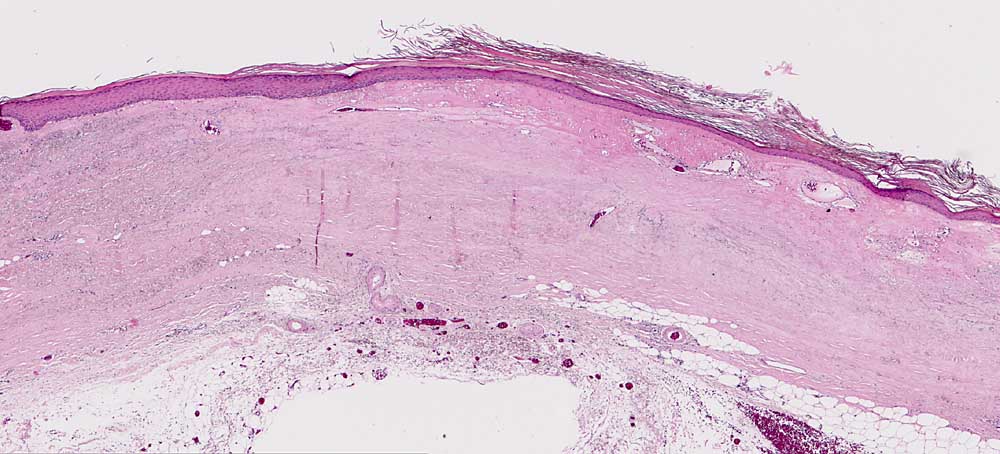

Chronische Radiodermatitis

Haut, Rumpf

Herdförmige Hyperkeratose. Vollständige Atrophie der Adnexe. Dermale Sklerose und fokale Elastose. Teleangiektasien. Fibröse Wandverdickung der Blutgefässe.

Fraktionierte Bestrahlung vor mehreren Jahren.

Histologie

25